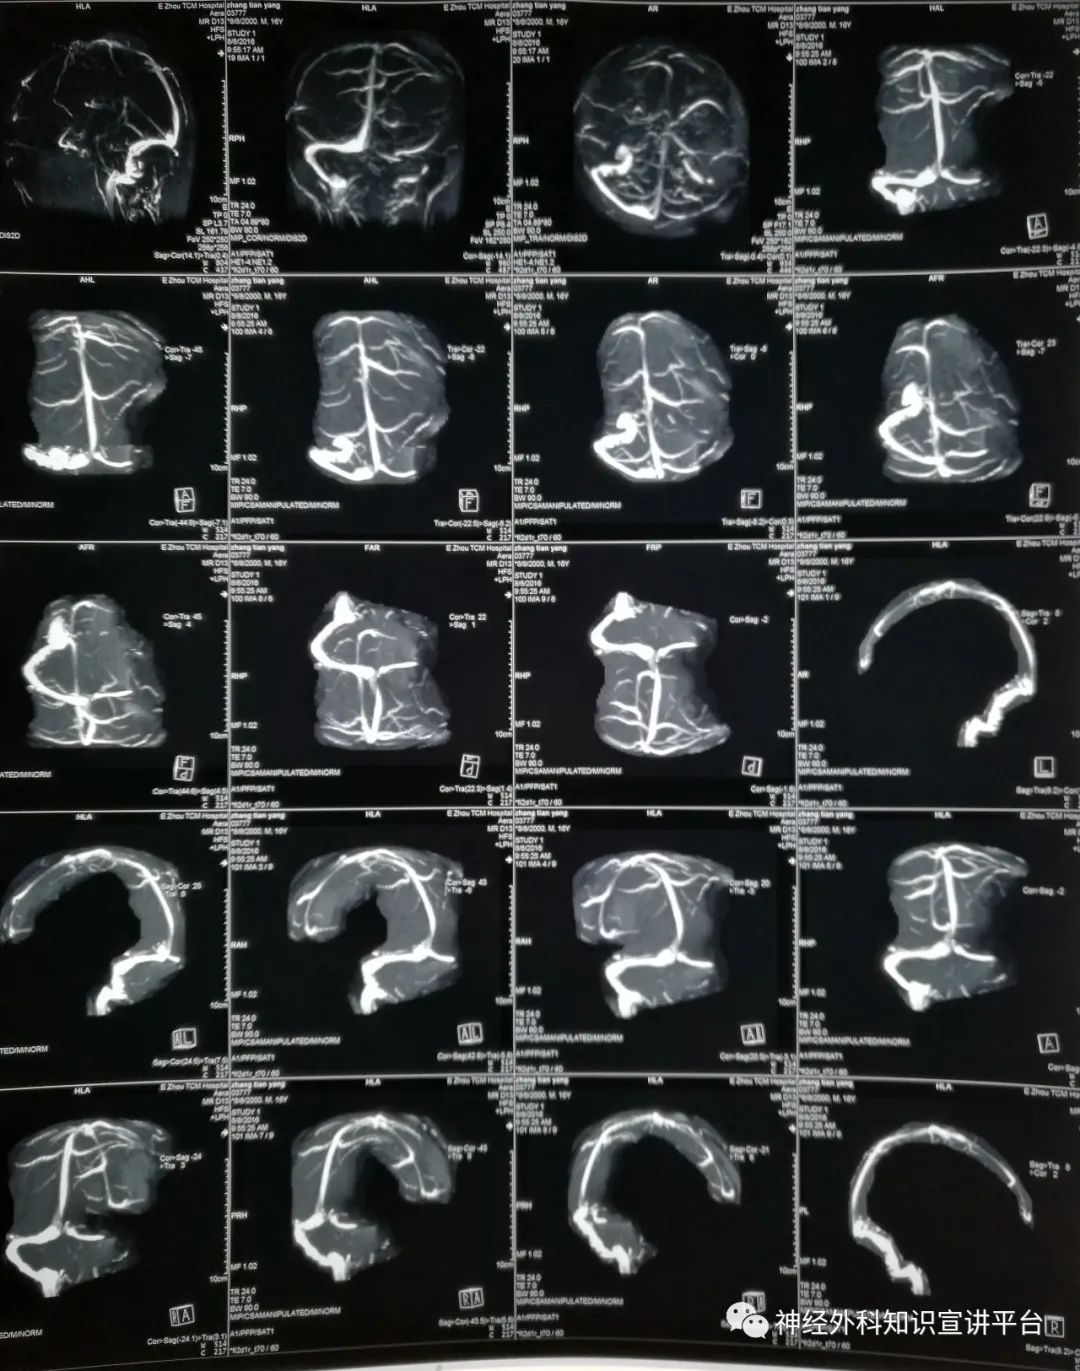

右侧颞叶蛛网膜囊肿分流术后8年,因恶心呕吐2周就诊

MRV排除静脉窦血栓形成